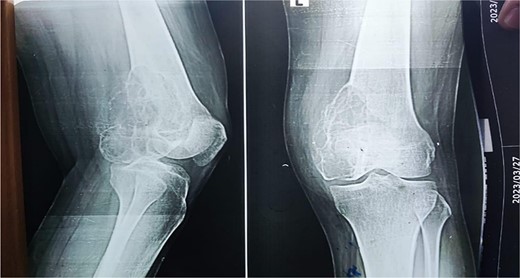

A 28-year-old female patient in her first trimester of pregnancy presented in our outpatient department with a complaint of persistent left knee pain for the past two years accompanied by a marked swelling around the left distal thigh region for the past 6 months. She had a previous X-ray that revealed an aggressive, Enneking stage III osteolytic lesion involving the medial femoral condyle, characterized by a shallow bubble appearance and a narrow zone of transition (Figs 1 and 2). A biopsy of the lesion was undertaken 6 months before the initial presentation and showed an aggressive GCT.

X-ray that was taken 4 months before presentation showing the tumor was very aggressive with a narrow zone of transition, and mass is progressively increased.